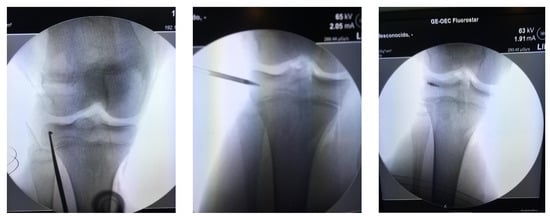

Indications for surgery included 24 patients with LET during Anterior Cruciate Ligament (ACL) reconstruction (in anterolateral margin of the proximal tibia at half of distance between head of fibula and Gerdy´s tubercle), two patients with extra-capsular MPFL reconstruction (on the medial margin of the patella´s border), three patients with quadriceps or patellar tendon repair (inside of the respective bone), and four with MCL repair (on the medial aspect of the proximal tibia, or close to the epicondyle targeting the anatomic footprint of MCL) (Figure 2).

Approximately 97% of extra-capsular repair cases with LET combined with ACL reconstruction relied on implants placed on the lateral tibial surface at a location point situated halfway between the fibular head and the Gerdy´s tubercle by means of a minimally invasive incision (Figure 4).

This technique also has the advantage that it can be used in pediatric patients, with the anchor implant placement achieved by radiographic control with a minimal incision and placing the anchor in the correct epiphyseal location to avoid injury of the cartilage growth zone and preserve the integrity of the bone growth plate (Figure 5). All patients returned to their usual work and sports activities without incidence of device-related or serious adverse events. In all cases, recovery of joint stability was achieved and complete recovery of full range of motion, except for the patient who underwent the manipulation under anesthesia who had a persistent 10° degree extension deficiency.

Figure 2. TWINFIX on the epicondyle footprint for medial collateral ligament, at the time of Anterior Cruciate Ligament ACL reconstruction.

Figure 4. Anterolateral fixation of the plasty at the time of lateral extra-articular (LET) (see footprint selection on the text). Arrows show femur and tibia tunnels with two interence screws fixation across out-in technique. Minimally invasive surgery for introducing the TWINFIX into the bone is showed.

Figure 5. ACL reconstruction on physis open patients. Under fluoroscopic control on the operating, selection of the footprint and intruction the TWINFIX for LET reconstruction.